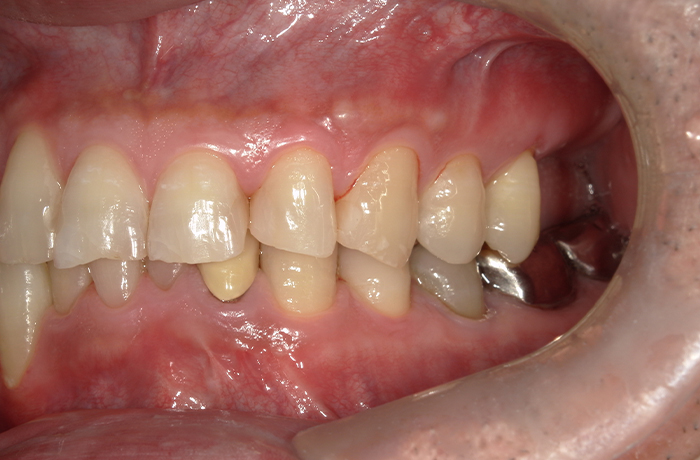

治療前

口腔内写真とレントゲン写真

左上6・7番欠損部は骨吸収が進行し、上顎洞底までの残存骨高径は5mm未満でした。

咬合支持が失われ、対合歯の挺出傾向がありました。